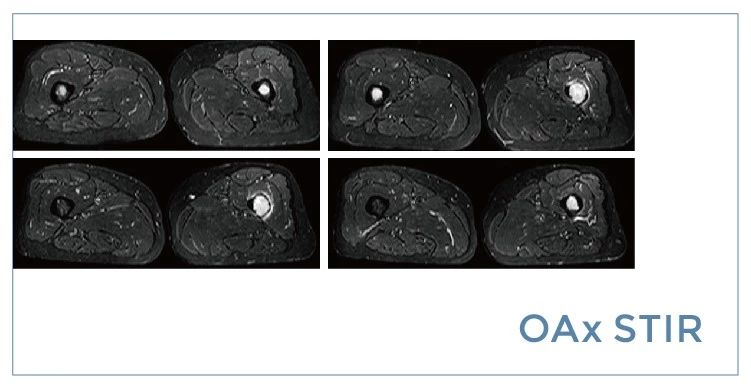

【朗润影像档案】20190712磁共振影像病例结果讨论